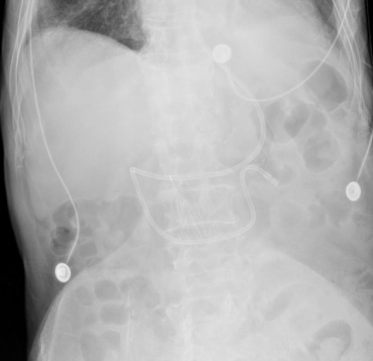

对于既往有误吸史、意识水平降低(镇静、颅内压升高)、神经肌肉疾病或呼吸系统及消化道结构异常、呕吐、机械通气或需要长时间水平仰卧、年龄>70岁、医护比不足、口腔护理不佳的呼吸危重症患者应考虑存在误吸高风险。患者存在2个误吸高风险因素,入院前有进食呛咳,考虑误吸史,年龄>70岁。因此,患者存在误吸高风险,应选择幽门后喂养,给予患者盲插鼻空肠管置入,并经胸部X线片验证,空肠管位置良好。此时可准备启动肠内营养治疗。

图片

2  胸部X线片验证鼻空肠管位置